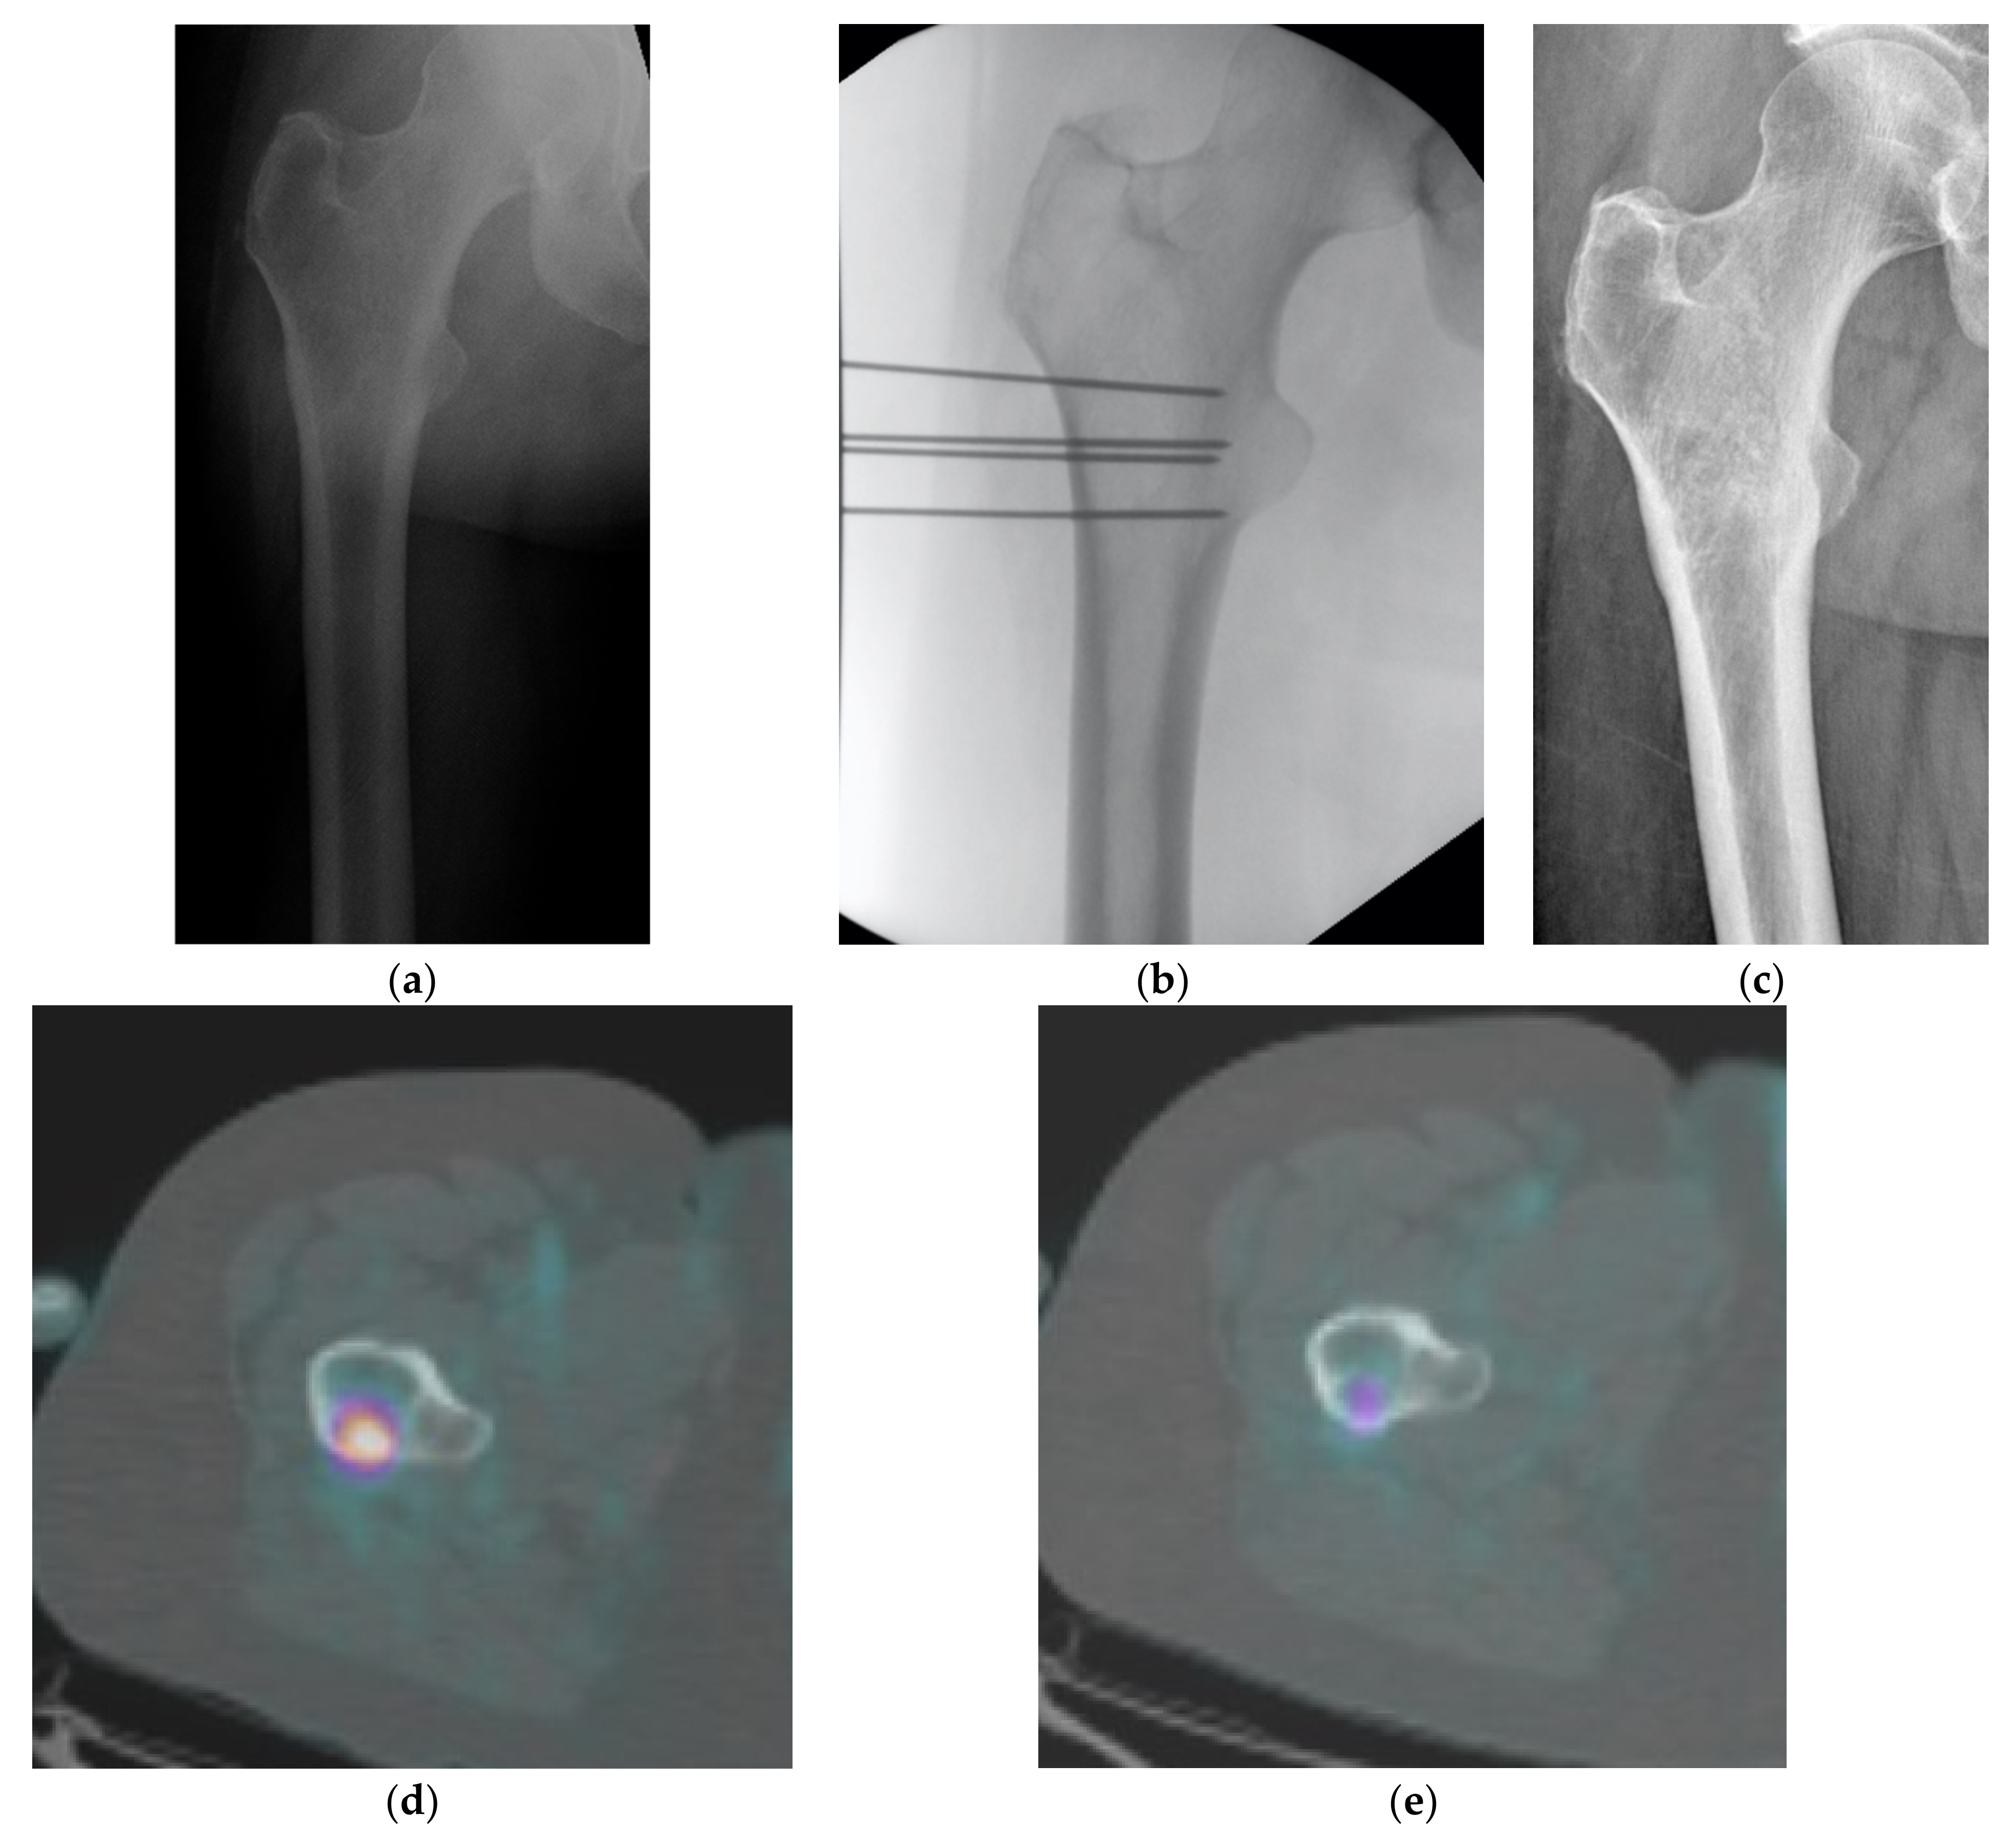

| Intensifier | 22 | 58% | |||

| CT | 16 | 42% | |||